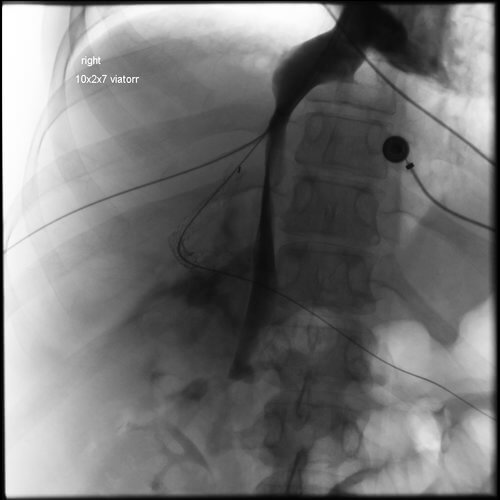

37 year old female with a known diagnosis of Budd-Chiari Syndrome who presented originally with a history of recurrent ascites. She experienced an acute upper GI bleeding secondary to varices near the GE junction, resulting in acute hypotension. The patient now presents for an urgent TIPS.

Comment: Attempts were made to place a TIPS in this patient from a hepatic vein approach. However, no recognizable hepatic veins were evident and no collaterals could be accessed percutaneously. As a result, we placed an 18g Chiba needle using a transhepatic approach from the midaxillary line; the needle was directed towards the RA-IVC junction. At the same time, the right internal jugular vein was accessed and a snare was positioned in the upper IVC. The needle was directed towards and passed through the snare. A guidewire was then advanced through the needle and that wire was pulled into the IJ sheath by the snare. A 5F sheath was then advanced from the liver into the IVC and a second wire was placed through the sheath and captured (in order to have a safety wire). At this point, the intrahepatic tract was dilated and a 10F sheath was advanced from the neck into this new tract through the liver. A CO2 venogram was then performed, followed by creation of a TIPS through this tract, extending from the right portal vein into IVC. Note that once the first stent was in place, it was short of the IVC so additional stents had to be placed. In addition, thrombus was noted at the origin of the right portal vein with preferential flow into the left portal vein. Mechanical thrombectomy had to be performed to insure portal vein and TIPS patency. At the conclusion of the procedure, the portosystemic pressure gradient decreased from 39 mm Hg to 10 mm Hg.